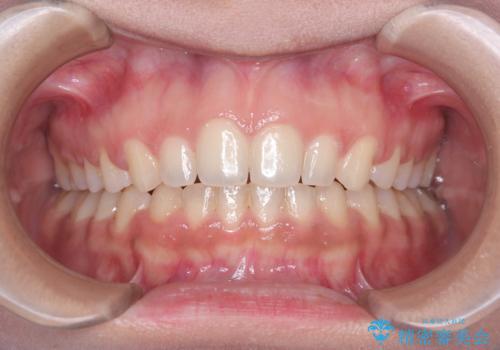

- 患者様は、前歯が出ている状態(上顎前突)と隙間を閉じたいというご希望で来院されました。診断の結果、骨格性の上顎前突が確認されたため、理想的には外科矯正が必要であることを説明しましたが、患者様の「非抜歯でできる範囲で治療を進めたい」という希望を尊重し、矯正治療計画を立てました。治療目標は、前歯の突出を可能な限り改善し、隙間を閉じることに重点を置きました。

本症例では、非抜歯での治療を選択したため、スペースを確保するためにIPR(歯間削合)を行い、歯列を整えました。オーバージェット(上の前歯と下の前歯の水平的なズレ)は残る結果となりましたが、見た目や機能の改善を重視し、患者様と治療計画を共有しながら進めました。治療中は、歯列全体のバランスと噛み合わせを考慮しつつ、矯正装置の適切な使用を徹底しました。当初の計画通りに治療を完了し、患者様にも満足していただけました。